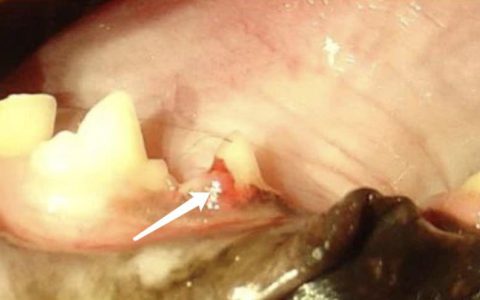

• 猫的牙齿破坏性吸收损伤(牙吸收)- FORLs

牙疼和蛀牙这两个问题,在人和猫身上完全是两回事儿。猫咪虽然是出了名的牙齿不好的动物,但是它也不会像人一样长蛀牙。 我们人如果有蛀牙的话,一般从牙齿的表面就能够看到。 但是猫的“蛀牙”却并非如此,猫的“蛀牙”会从牙龈线以上开始,然后逐步向牙髓中心扩散,由内而外,最后,严重阶段,你才可能在牙齿表面发现。 猫咪的这种类型的“蛀牙”,我们将之称为“猫牙齿破坏性吸收损…